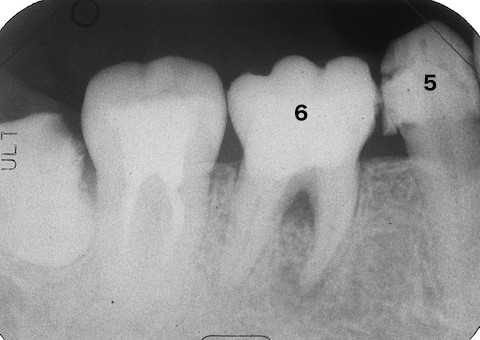

残根上のCR8 2025.10.28